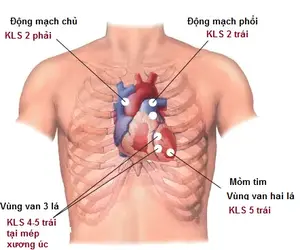

Thằng nào hiểu biết giải phẫu cơ thể người giải thích hộ tao sao thằng này nó vẫn sống được là như nào. Liệu nó có sống được không hay không có cơ hội?

Thằng nào hiểu biết giải phẫu cơ thể người giải thích hộ tao sao thằng này nó vẫn sống được là như nào. Liệu nó có sống được không hay không có cơ hội?